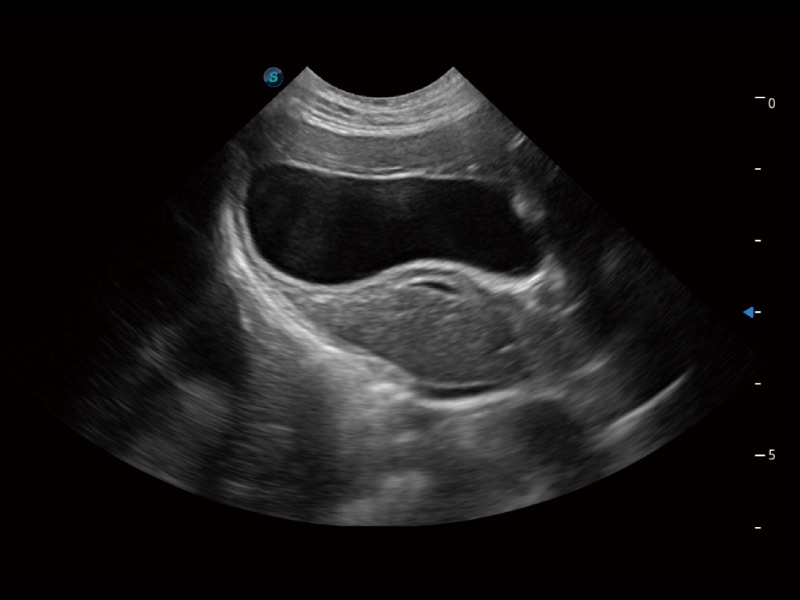

动物是人类最亲密的朋友和最值得信赖的伙伴。乐玩lewin国际也一直致力于探索动物专用的超声影像解决方案。全新推出的ProPet系列,是乐玩lewin国际在动物超声影像智能化、专业化、精准化的一次跨越式革新。动物不能用言语来表述自己的不适,通过超声影像,ProPet系列搭建了动物医生与不同物种沟通的“桥梁”,为动物医生注入了“治愈之力”。 ProPet 70将是您值得信赖的超声伙伴。它配备了复合材料线阵探头,帮助动物医生获得卓越精准的临床图像。同时ProPet 70直观便捷的操作体验以及专业的测量工具,可为不同体型和生理结构的动物带来全面临床评估,切实为动物医生提供智能、专业、精准的超声影像解决方案。

ProPet 70 进一步提升了微米成像算法,更加注重对基础原始图像的还原和保留,在有效减少斑点噪声、增强组织边界显示的同时,避免过度优化丟失真实的解剖信息。

ProPet 70专为动物医生设计,对不同的动物体型和生理结构作出了针对性的优化。通过动物影像专用软件,可满足个性化的应用需求,帮助动物医生获得更精确的诊断数据。

为精细结构及组织边缘提供高清晰度的图像和更大的成像视野。帮助减轻医生的用眼疲劳,快速精准获得测量的数据。